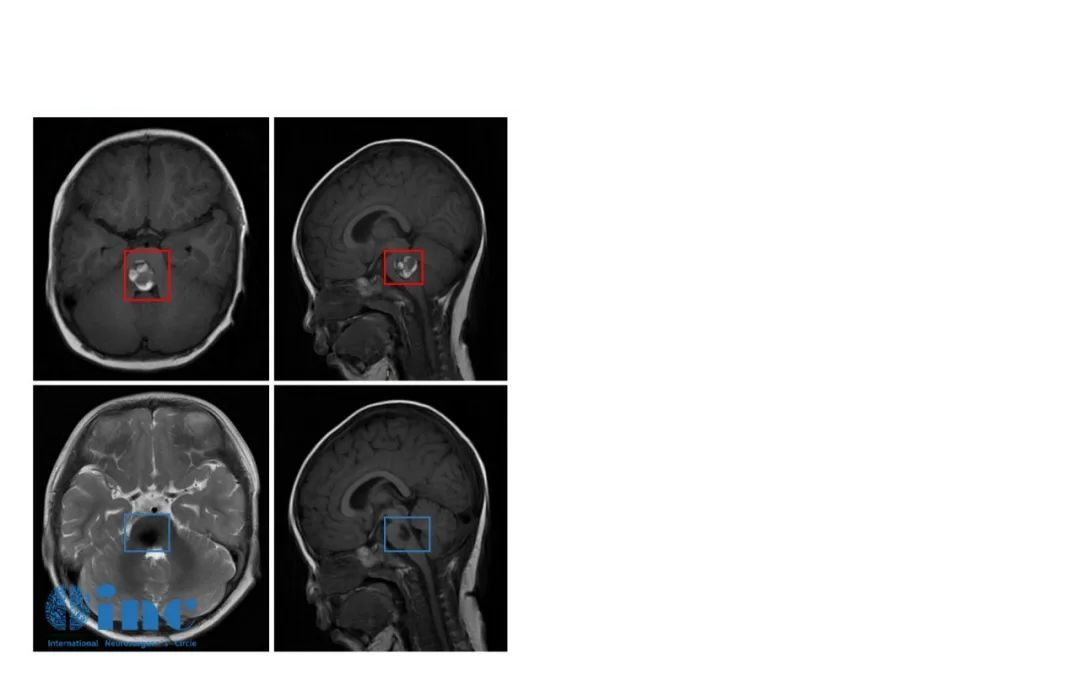

与儿童医院协作的手术医生围绕病情展开了充分的讨论和评估,并根据患者病变的特点较终确定了相对创伤小的手术入路和手术方案。手术由巴特朗菲教授亲自操刀,儿童医院神经外科医生从旁配合,在电生理监测及高倍显微镜下,巴特朗菲教授游刃有余地避开了脑干中的一些重要神经核团、传导束,先将血肿清除,再慢慢地将2cm大小的脑干桥脑海绵状血管瘤完全剥离,整个手术历经了4个小时。

(伊伊术前术后对比)

术后二天,经历了如此高难度手术的伊伊就出了ICU,她术前频发的不自主扭头动作都消失,左侧眼睑稍下垂较前开始好转,双眼斜视较前好转,眼球活动度正常,其他术前症状均出现缓慢好转。巴教授也时常来伊伊病房看望这个可爱的孩子,“完全没有脑瘤教授的架子,特别亲切”,伊伊妈妈忍不住感慨。

而因为巴教授的手术技术,术后一周伊伊就出院了,术后一个半月复查,原有的斜视、走路不稳症状都消失了,面瘫减轻,行动能力完全正常,没出现任何新的并发症。